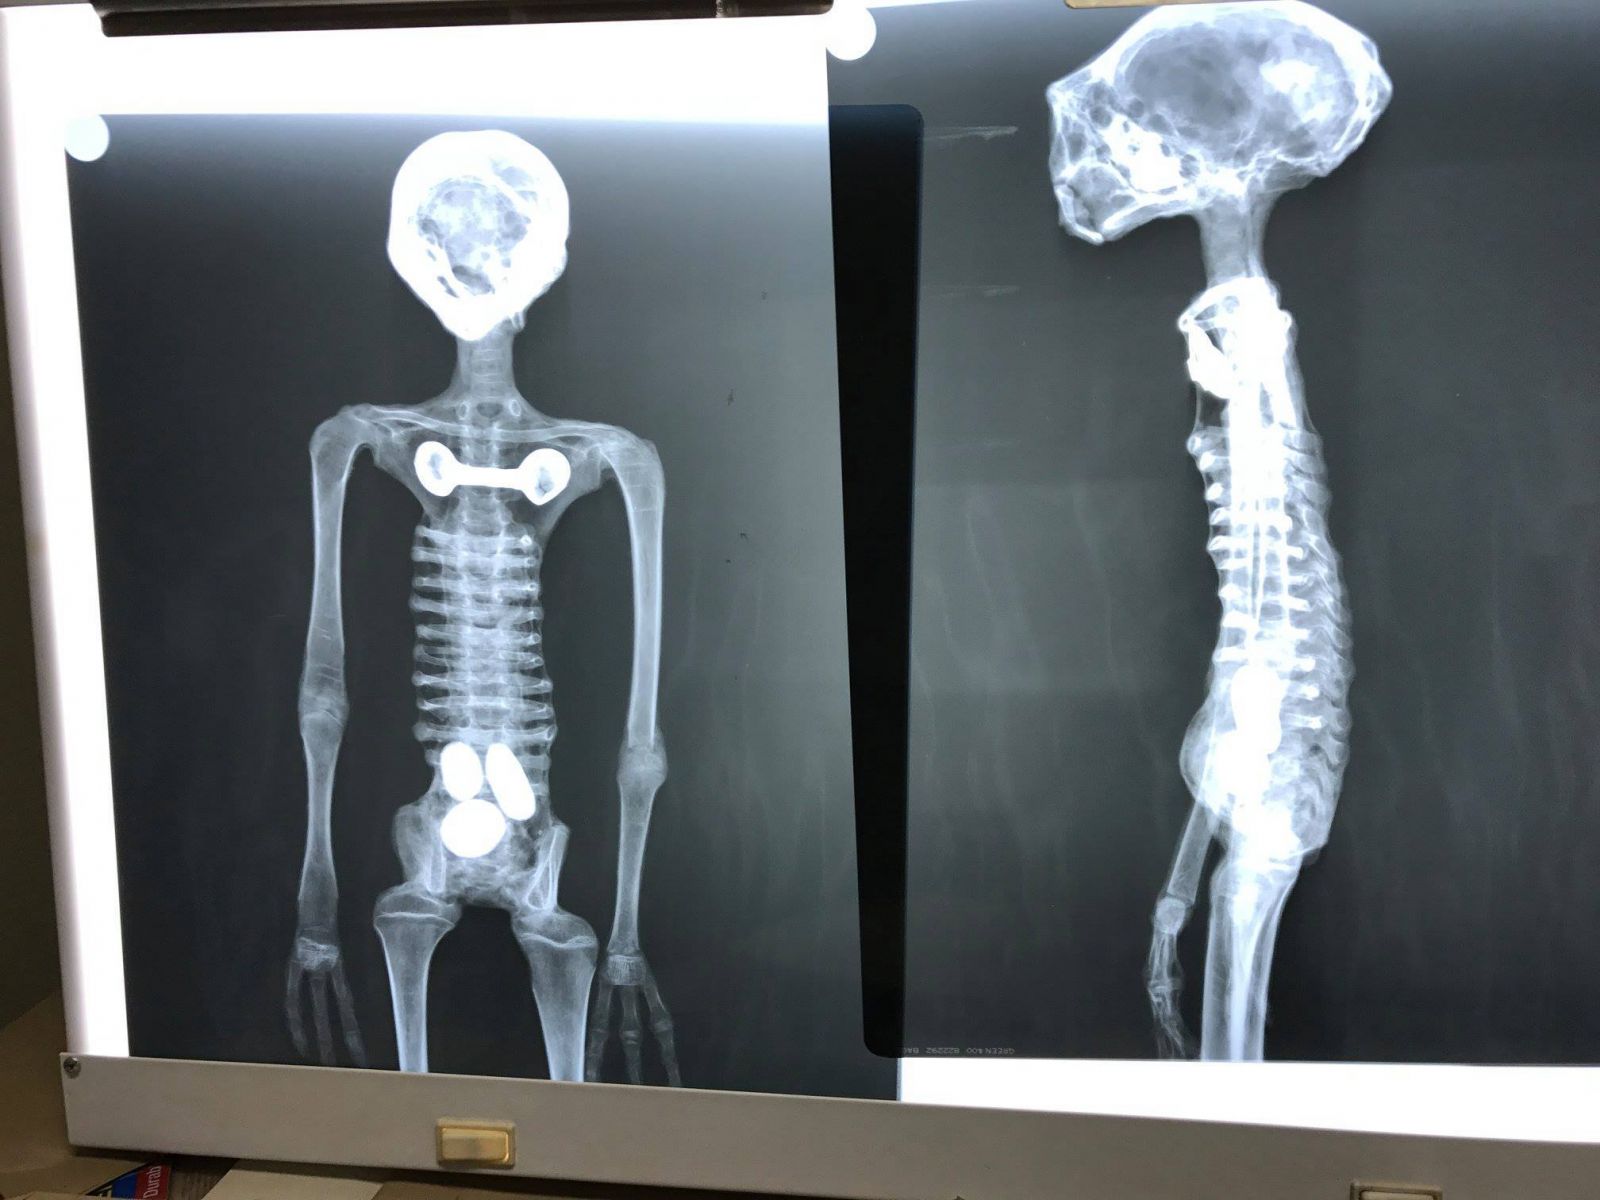

Các nhà khoa học sử dụng X quang để xem bàn tay ba ngón. Họ nói rằng chúng chính là xương người được ghép lại với nhau.

Một số hình ảnh tham khảo: